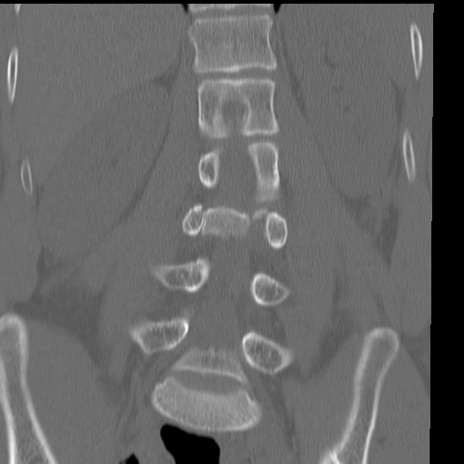

症例3 腰椎CT(冠状断像)

腰椎CT

横断像

3D再構成